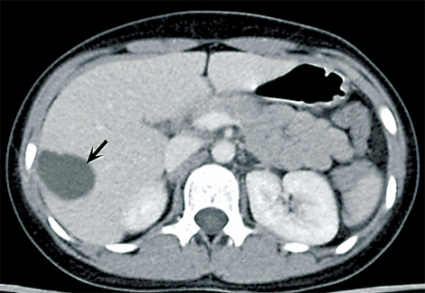

Fall 2. En 34-årig man från Tunisien sökte vård för buksmärta och hög feber. Patienten var ikterisk och visade tecken till gallstas. Antibiotikabehandling inleddes då den kliniska bilden talade för kolangit. Utredning med ultraljud och DT påvisade två cystiska förändringar i levern (5 respektive 6 cm stora), båda såg ut som ekinokockcystor. Blodprov visade stegrat CRP och eosinofili. Serologisk diagnostik bekräftade diagnosen. Gallvägarna avlastades med stentning via endoskopisk retrograd kolangiopankreatografi (ERCP) på grund av en intrahepatisk striktur (Figur 2). Behandlingen förbättrade initialt kolangiten, men patienten fick flera recidiv.

Radiologisk utredning av ekinokockcystor har flera målsättningar. Den ska bidra till diagnostiken och till en anatomisk kartläggning av utbredning och eventuella komplikationer, bedöma cystans viabilitet och underlätta preoperativ planering. Den radiologiska diagnostiken av ekinokockcystor i levern har centrerats runt ultraljud men har på senare tid ofta ersatts med DT och MR. Radiologiska fynd som talar för ekinokockcysta utgörs framför allt av cystvägg med dubbelkontur, multivesikulärt utseende och väggförkalkningar (talar för inaktiv cysta). Viktigt att komma ihåg är att kalcifiering av väggen förekommer inte bara vid inaktiva (CE4 och CE5) cystor utan även i upp till 50 procent vid alla stadier [7]. WHO-klassifikationen av ekinokockcystor grundas på ultraljudsundersökning men kan överföras till antingen DT eller MR [2, 3]. Cystans relation till gallvägar, kärl och extrahepatisk vävnad bedöms enklast med DT eller MR. Om fistulering till gallvägar misstänks kan MR med kolangiopankreatikografisekvenser och i vissa fall endoskopisk retrograd kolangiopankreatikografi (ERCP) bidra till noggrann anatomisk kartläggning inför planerad resektion [8].